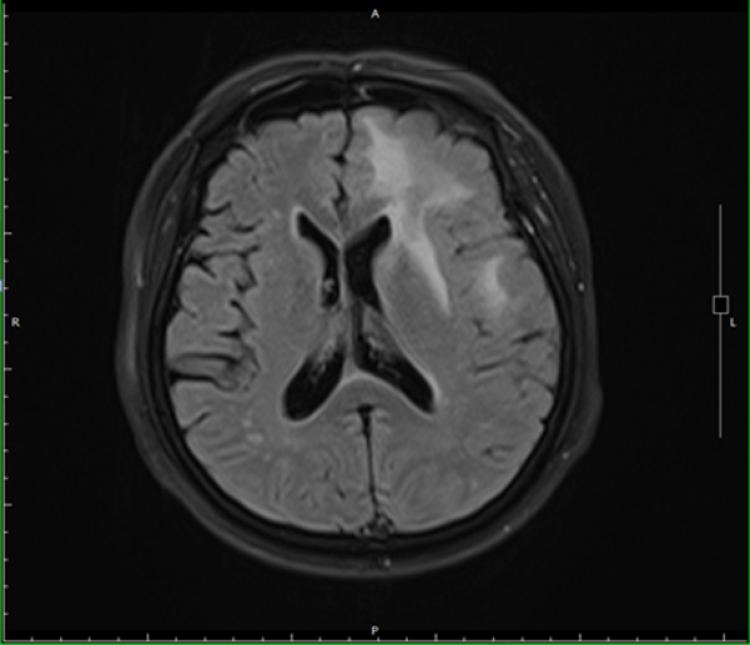

2020年8月,徐老伯起床时因突发头晕、头痛、恶心,从床上跌落。家人随即将徐老伯送至新华医院急诊就诊,完善头颅MRI提示:左侧额叶、胼胝体多发占位,考虑恶性或转移可能。徐老伯在神经外科完成了颅内肿瘤切除术和开颅颅内减压术,临床结合病理及影像学检查确诊,徐老伯罹患原发中枢神经系统弥漫大B淋巴瘤,并存在CD79b、 Myd88等不良预后相关的基因突变。